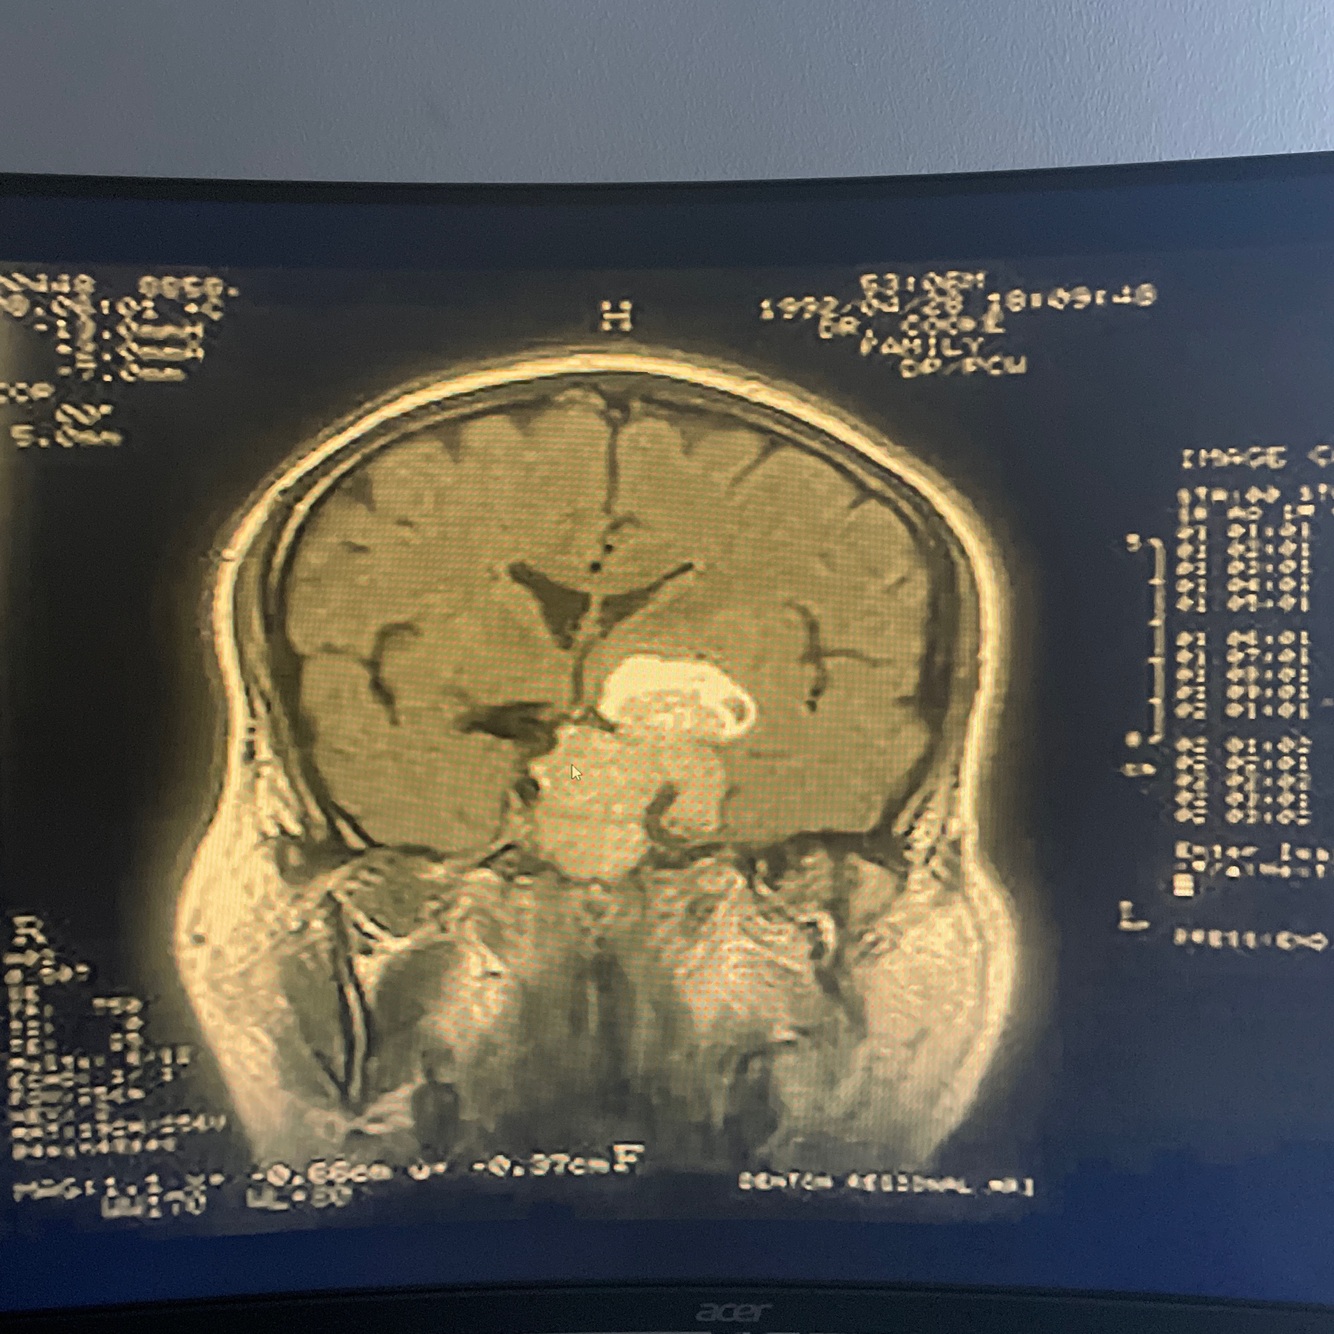

Craniopharingioma most common cause ofhypituatarism in children